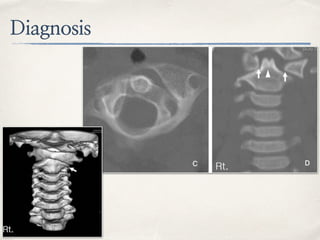

Diagnosis

✤ Imaging

✤ Open-mouth plain film show

asymmetrical of lateral of

C1 to odontoid process

✤ Lateral plain film show

lateral mass of C1

projecting anterior to

odontoid process >> “wink”

sign

✤ Cervical spine CT is recommended for diagnosis of

AARS

✤ Contrast injection for evaluating of vertebral artery

✤ MRI can be used for evaluating of transverse ligament

and cord compression